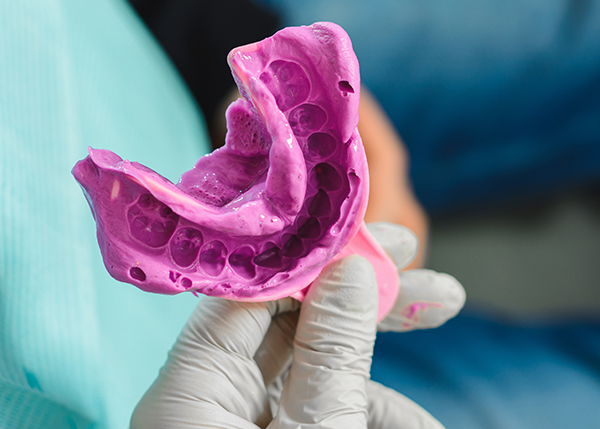

치과보존과 전문의의

미세현미경을 이용한 자연치아 살리기 -

자연치아를 보존하고 살리는 것보다 더 좋은 치료는 없습니다.

치아살리는치과에서는 미세현미경을 이용한 정밀 진단 및 고난도 신경치료 등

치아보존 치료가 가능합니다.